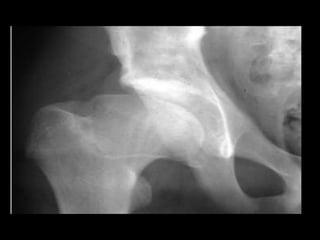

X-Ray –AP & Frog leg Lat view

XRAY:

Early radiographic signs:

• Failure of femoral ossific

nucleus to grow

• Widening of medial joint

space

• “Crescent sign”

• Irregular physeal plate

• Blurry/ radiolucent

Metaphysis

INITIAL STAGE: